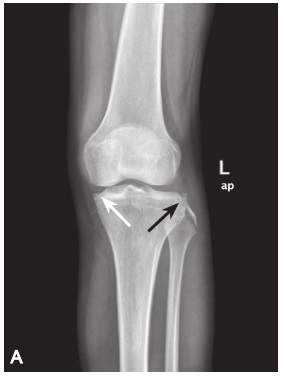

反Segond 骨折:在膝关节X 线前后位或 CT、MRI 冠状位显示,表现为胫骨平台内侧缘撕脱性骨折。碎骨片常向外移位,可伴后交叉韧带损伤;MRI 可观察膝关节前交叉韧带、内侧副韧带和内侧半月板损伤情况。

A. 膝关节 X 线前后位片。白色箭头示反 Segond 骨折。黑色箭头显示胫骨平台外侧及腓骨头骨折。B. 膝关节 MRI。矢状位 PDWI:ACL 和 PCL 损伤后胫骨水肿;C. 冠状位 T2WI:胫骨平台内侧撕脱性骨折(反 Segond 骨折)和胫骨平台外侧撕脱骨折